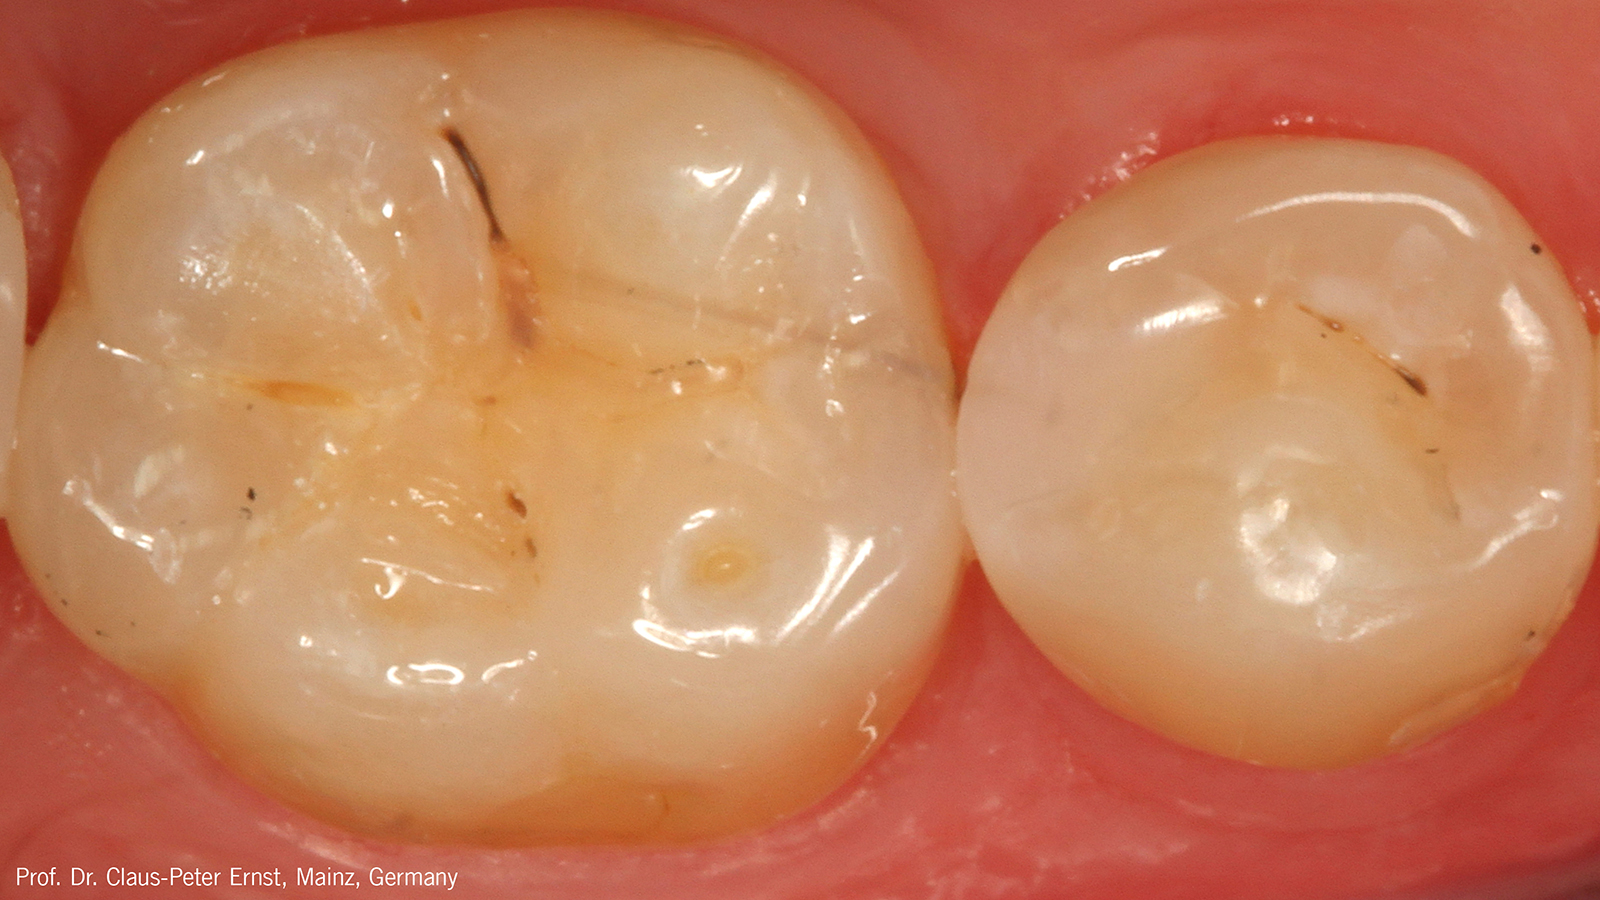

Charisma Diamond/ Charisma Topaz ONE Shade blends seamlessly into the surrounding dentition, independent of the tooth shade, enabling restorations to simply disappear. The universal composites for everyday restorations offer a new one-shade solution within the Charisma family for the majority of everyday cases.

Charisma Diamond/Charisma Topaz ONE Shade determines the shade of the restoration by absorbing the lightwaves that are reflected by the surrounding tooth shade.

The ONE shade has been optimised to deliver the perfect balance of chroma and translucency that allows the restoration to become virtually invisible. Therefore, the ONE shade can be used with confidence in any Class I and Class II restoration. And this colour adaptation is what we call Adaptive Light Matching.